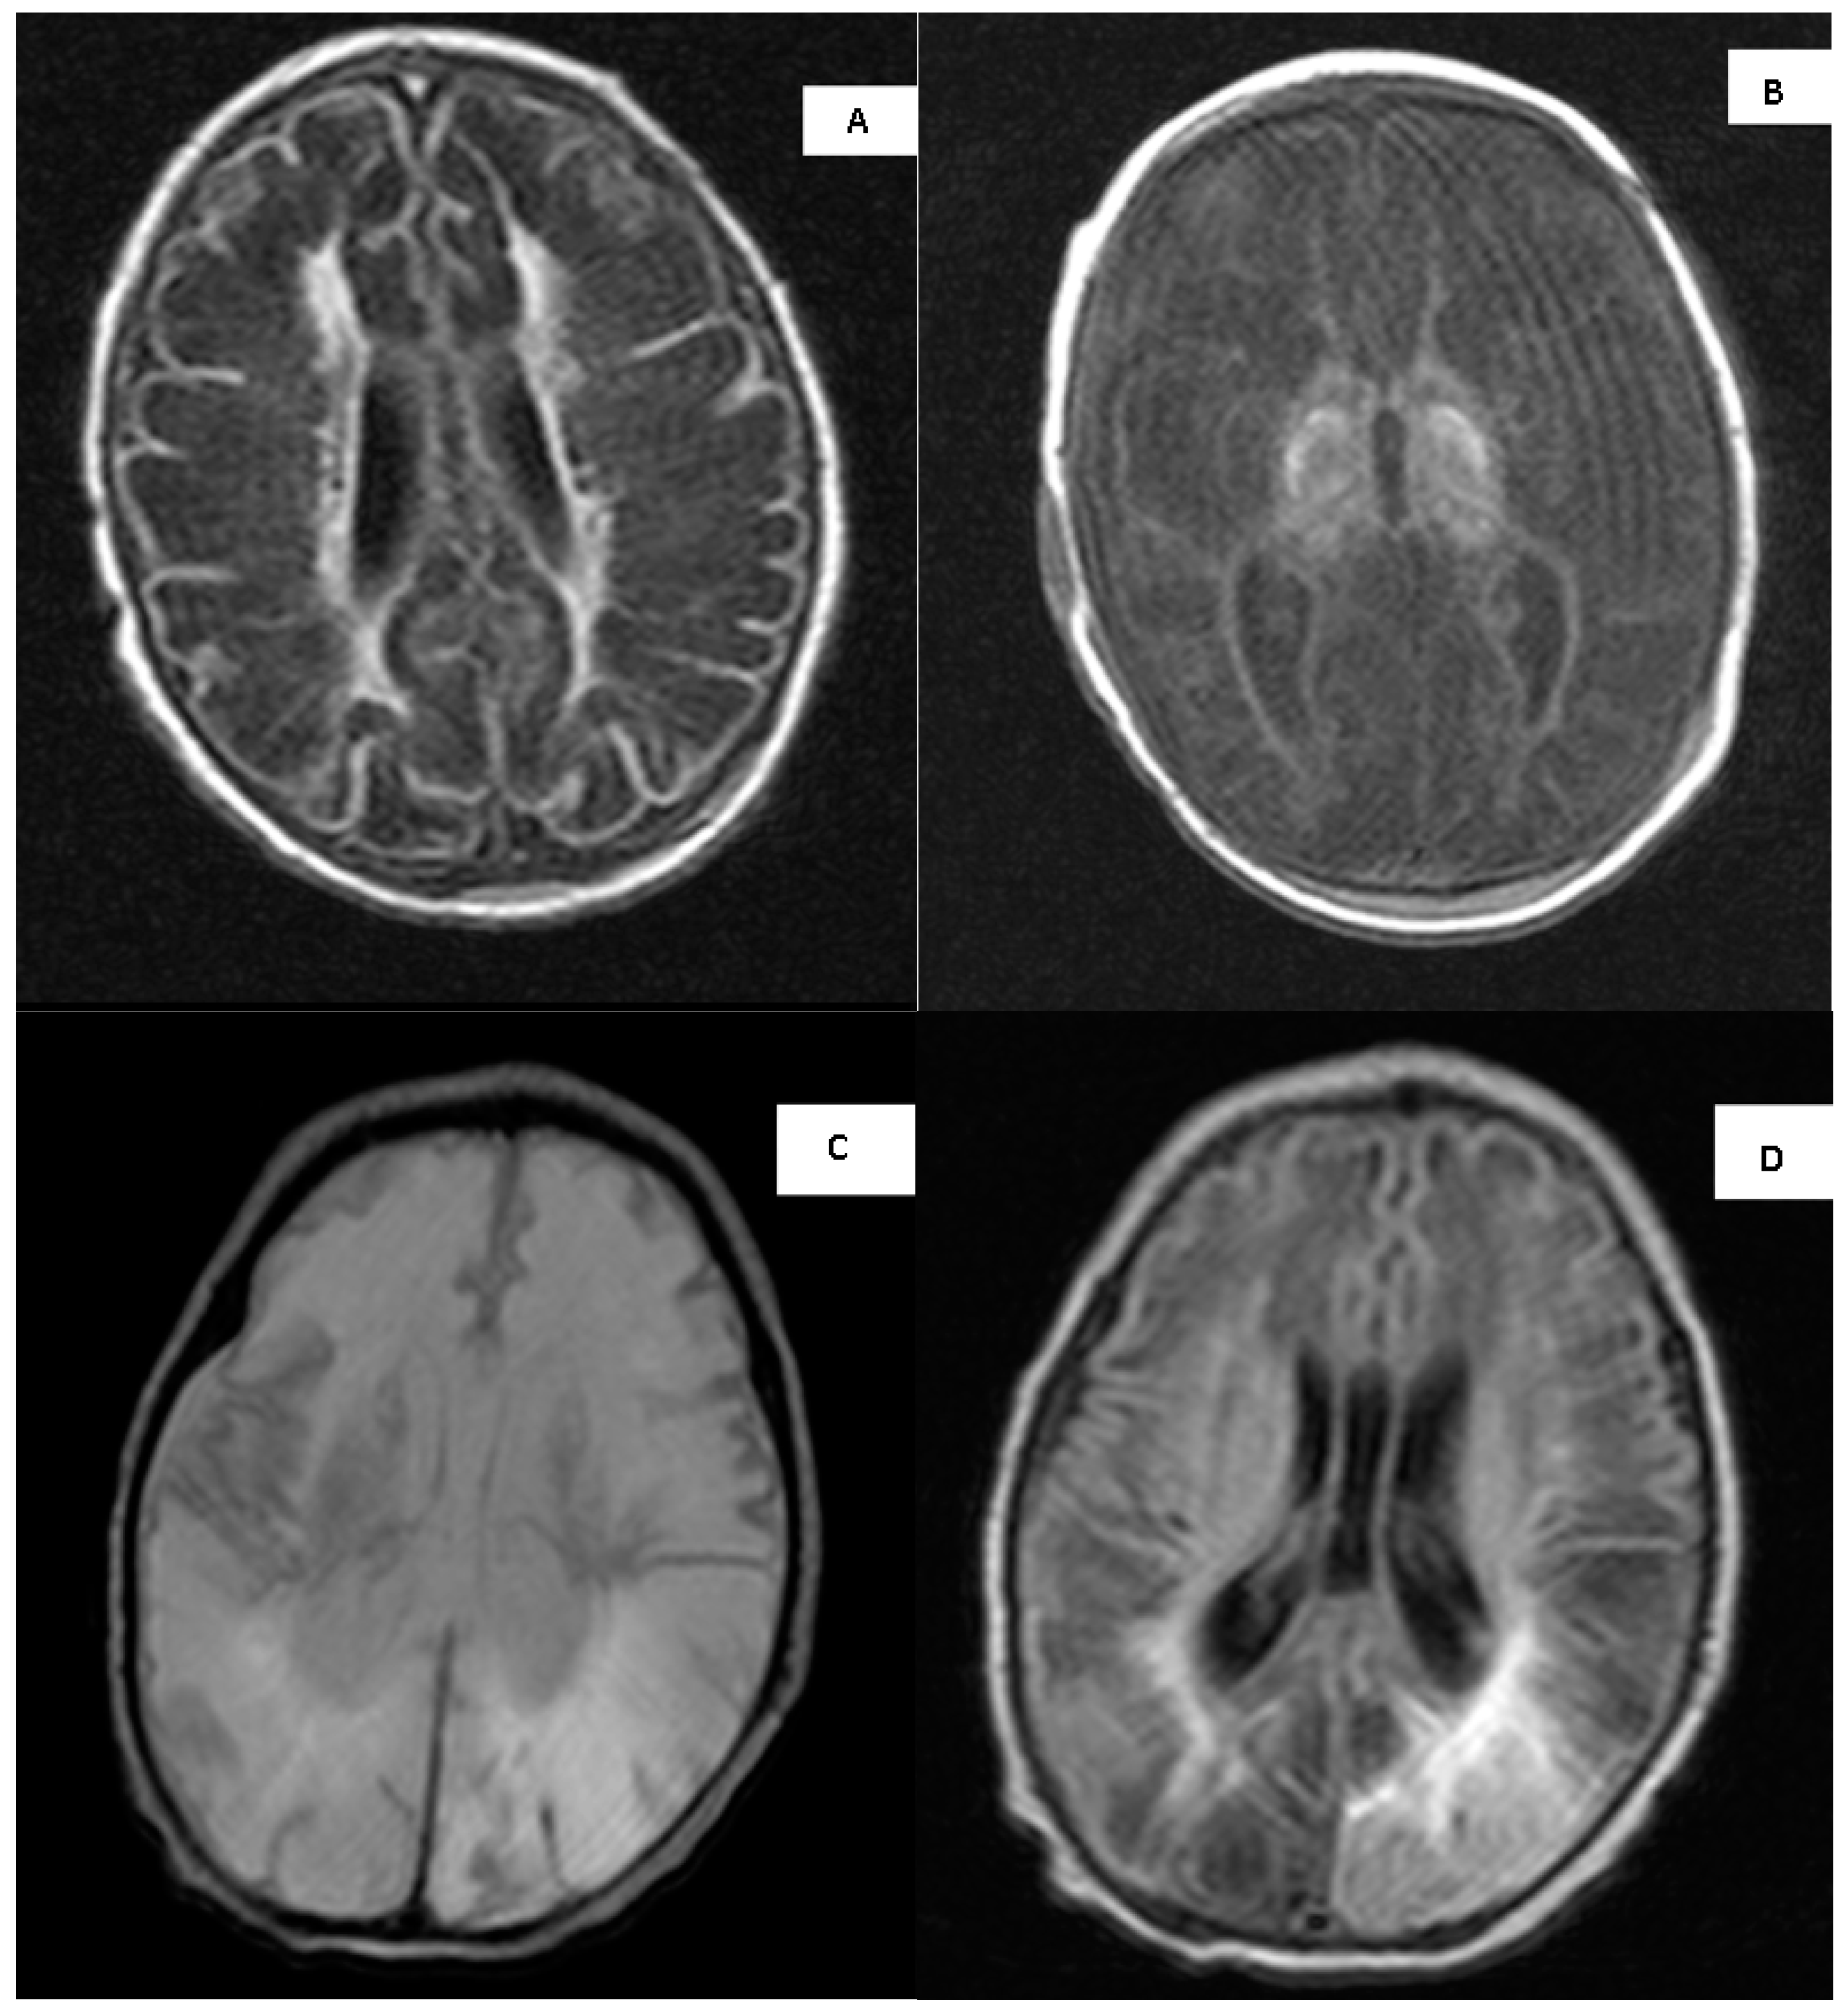

3.10. MRI Imaging